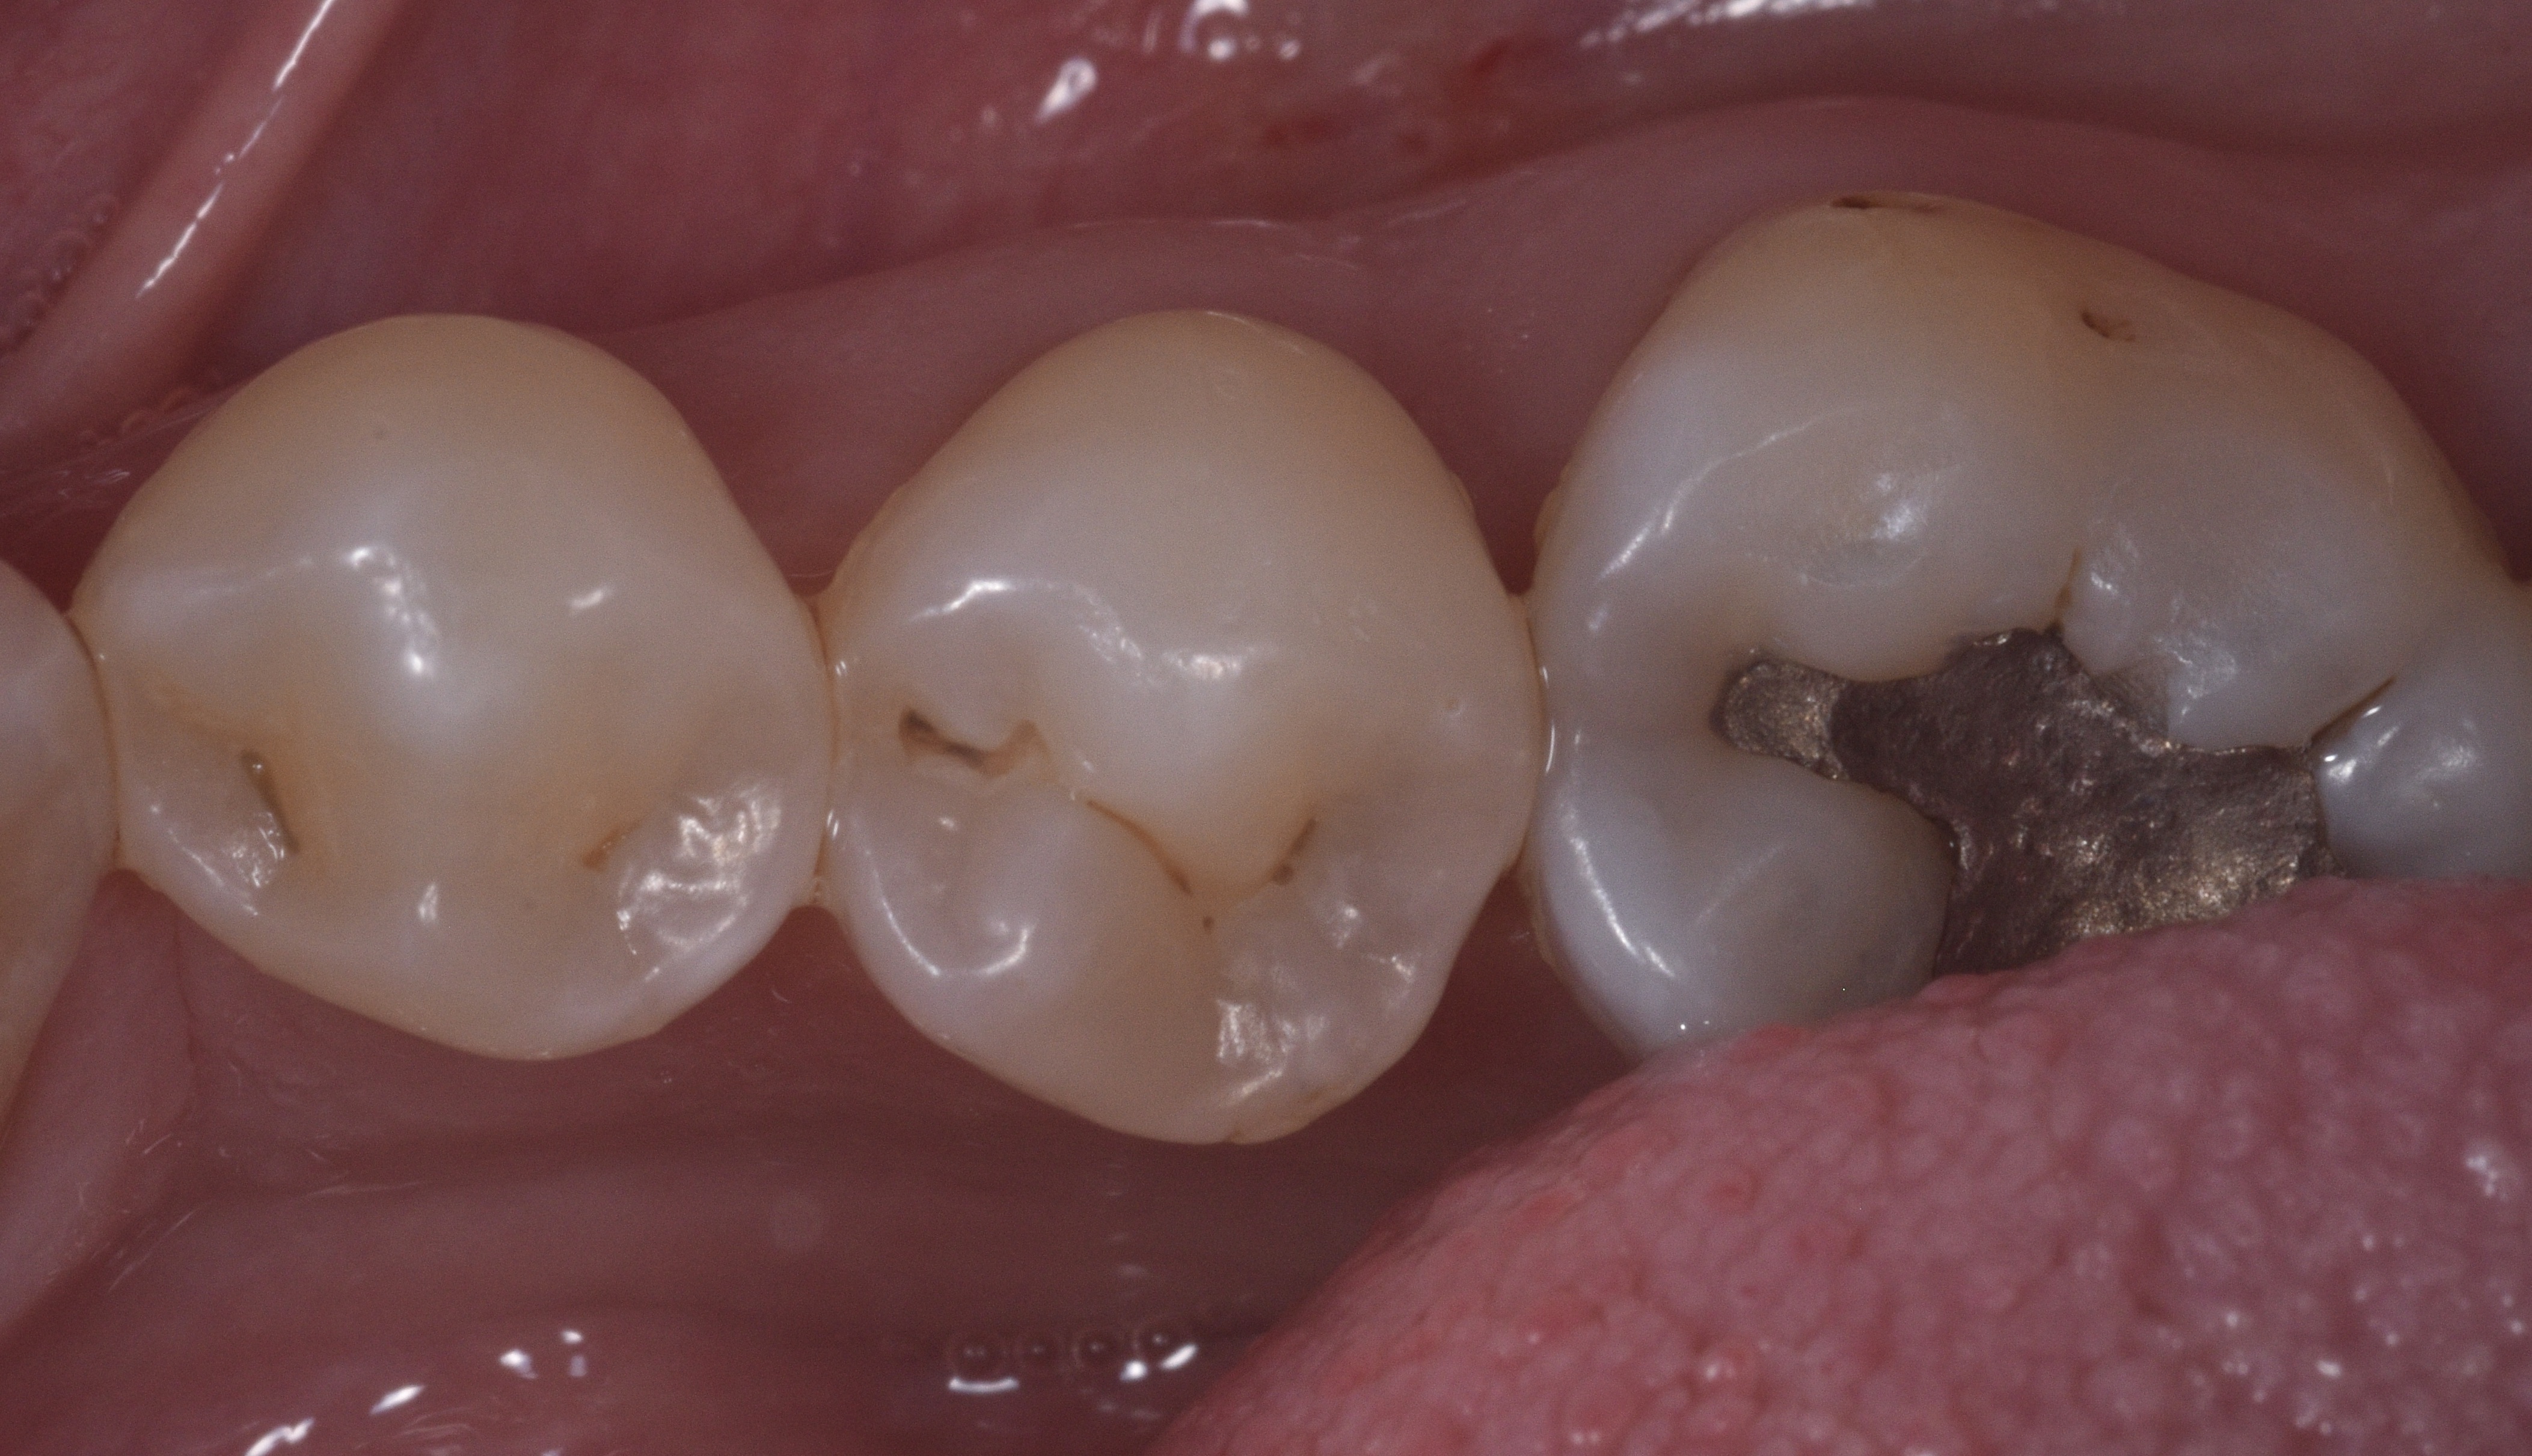

Figure 12 demonstrates the completion of the DME with a single horizontal layer of Harmonize composite (Kerr), while Figure 13 shows the subsequent composite layer used to build the proximal wall. The completed restoration is depicted in Figure 14, and Figure 15 displays both teeth after finishing and polishing, highlighting the natural contours of the embrasures and the anatomical IP contact achieved.

Figure 14. Completed restoration shown. Figure 15. Both teeth after finishing and polishing.